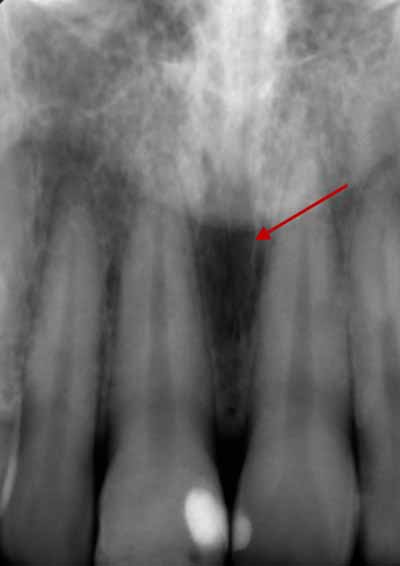

歯の発育がまだ完了していない子供や青少年では、歯列の発育段階に応じて歯の外観が変化すると考えられます。歯根の発達が不完全な歯は根尖性歯周炎に似ている可能性があるため、レントゲン写真で根尖周囲の変化を確認する際には、この点に留意することが重要です (画像4を参照)。